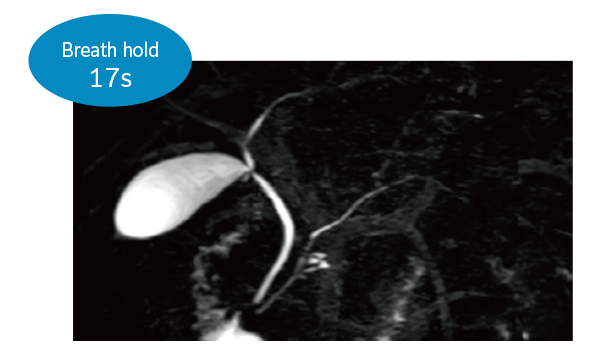

IP-RAPID x DLR Plus gives you the flexibility to shorten respiratory gated series or even replace them with breath-holds, depending on the patient’s situation. This gives you more options and a wider range of examinations to choose from.

3DMRCP (Breath hold)

3DMRCP Navigator gating (Navi)

3DMRCP (Respiratory synchronization)